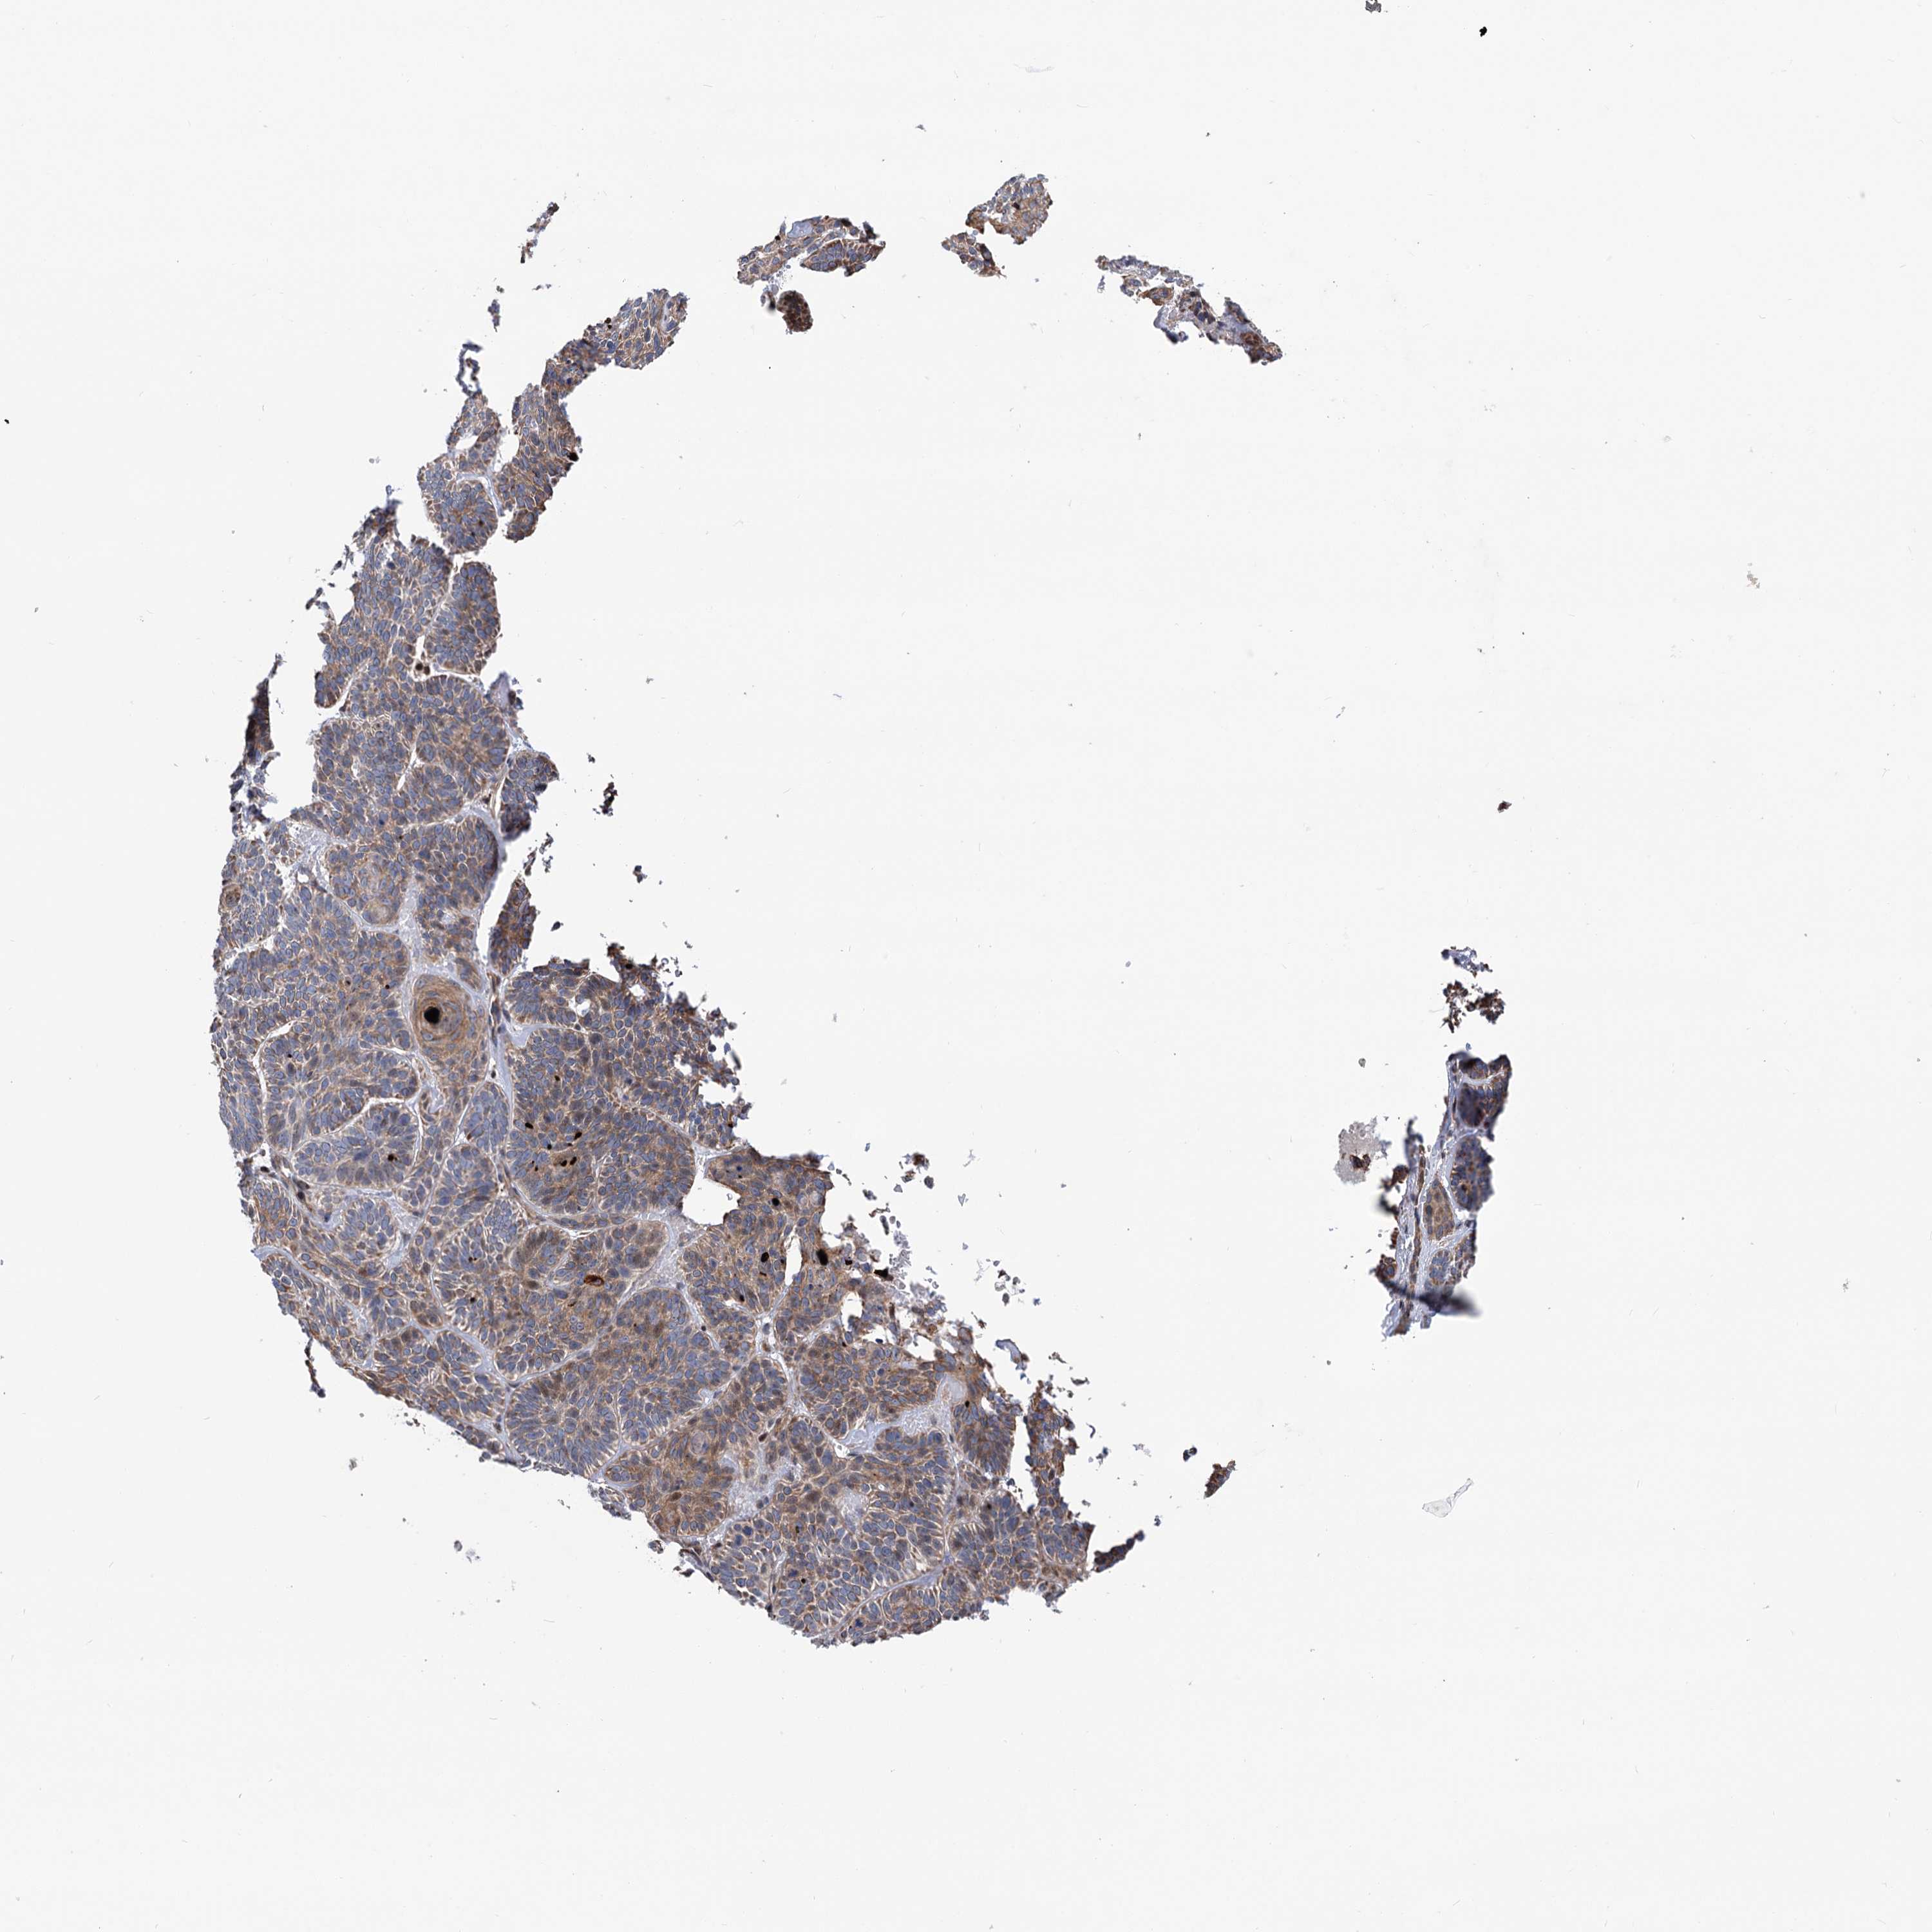

SKIN CANCER - Protein expressioni

A mouse-over function shows sample information and annotation data. Click on an image to view it in a full screen mode. Samples can be filtered based on level of antibody staining by selecting one or several of the following categories: high, medium, low and not detected. The assay and annotation is described here.

Antibody stainingi

Antibody staining in the annotated cell types in the current human tissue is reported as not detected, low, medium, or high, based on conventional immunohistochemistry profiling in selected tissues. This score is based on the combination of the staining intensity and fraction of stained cells.

Each image is clickable and will lead to virtual microscopy that enables deeper exploration of all samples and also displays staining intensity scores, fraction scores and subcellular localization as well as patient and tissue information for each sample.

Antibody HPA038838

Antibody HPA046727

Staining

High

Medium

Low

Not detected

Intensity

Strong

Moderate

Weak

Negative

Quantity

>75%

75%-25%

<25%

None

Location

Nuclear

Cytoplasmic/membranous

Cytoplasmic/membranous,nuclear

Basal cell carcinoma

Squamous cell carcinoma, NOS

Squamous cell carcinoma, metastatic, NOS